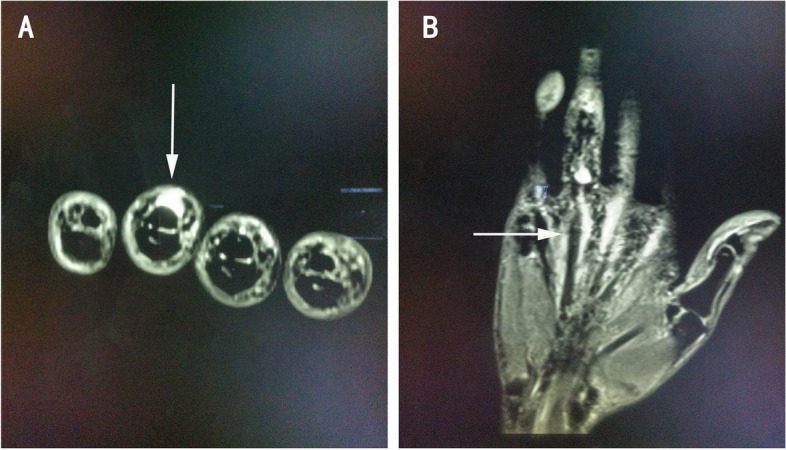

On the ultrasound image, extensor tendon interruption and surrounding edema was detected in the fourth and fifth fingers of the right hand (Fig. 3). On MRI T2-weighted image, a discontinuous high signal in the tendons of the fourth and fifth fingers and edema in the surrounding tissue were detected (Fig. 4). Both MRI and ultrasound results suggested tendon rupture of the right fourth and fifth fingers with remarkable inflammation in the tendons and surrounding tissue.

Fig. 4.

MRI T2-weighted image shows in-continuous high signal in finger extensor tendon (A) and edema in the surrounding tissue (B)